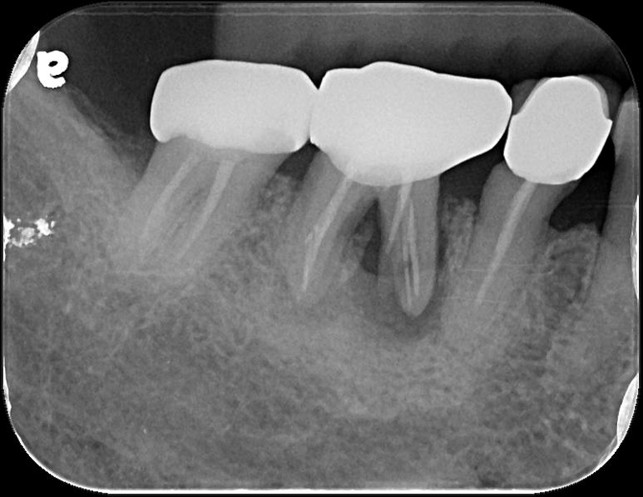

治療後根尖片

術前、術後比較